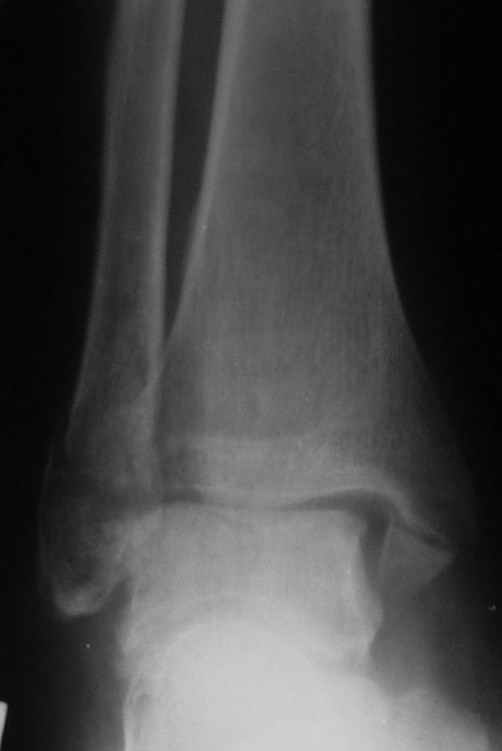

Если до сих ничего не сделано, с артродезом сустава в данный момент я бы повременил, на выставленных январских снимках хорошо сохранившийся сустав, а в "мортиз" (трехчетвертной) и на боковых снимках не менее 5 мм укорочение малоберцовой кости. Косые переломы лучше фиксировать пластинами, как то мы разбирали случай, где было отмечено, что это закон "таранная кость всегда следует за малоберцовой".

В данном случаи я бы уговорил больного на реконструкцию, для этого после удаления шурупов, спереди очистить от рубцов синдесмоз, несросшуюся наружную лодыжку - остеотомия по линии перелома и компрессирующий (lagging technique) кортикальный шуруп 3.5 мм по поперечнику остеотомии. Следующий этап - восстановление длины малоберцовой за счет удлинения, сделать поперечную остеотомию где-то на уровне сантиметр выше вашего синдесмозного шурупа, наложить длинную пластинку, прикрепить пластину за дистальный конец двумя или тремя шурупами; сохраняя контакт пластины с костью, имеющимся

compression&tension device AO system (при отсутствии любой lamina spreader подойдет, создать дистанцию между пластиной и шурупом, проведенным проксимальнее пластины) толкая проксимальный отдел пластины, низвести пластину, мортиз рентгенограмма подскажет на сколько. Если заранее сделать предоперационный план (ренгенограмма другой стороны), тогда точно можно определить, на сколько вам необходимо сделать поперечную остеотомию малоберцовой кости, для закрытия создавшегося дефекта.

Недавний случай, больной 56 лет получил политравму в Англии, после переведен в США, где его успешно лечил местный ортопед, огромная статья в газете об успешной операции, своеобразный пиар, из-за того, что больной был американский пожарник на пенсии, и за его переезд было заплачено международным пожарным союзом, короче по другим показаниям перевели больного в наш университетский госпиталь.

После 5-6 недели после травмы сделана повторная операция, обошлись без удлинения малоберцовой.